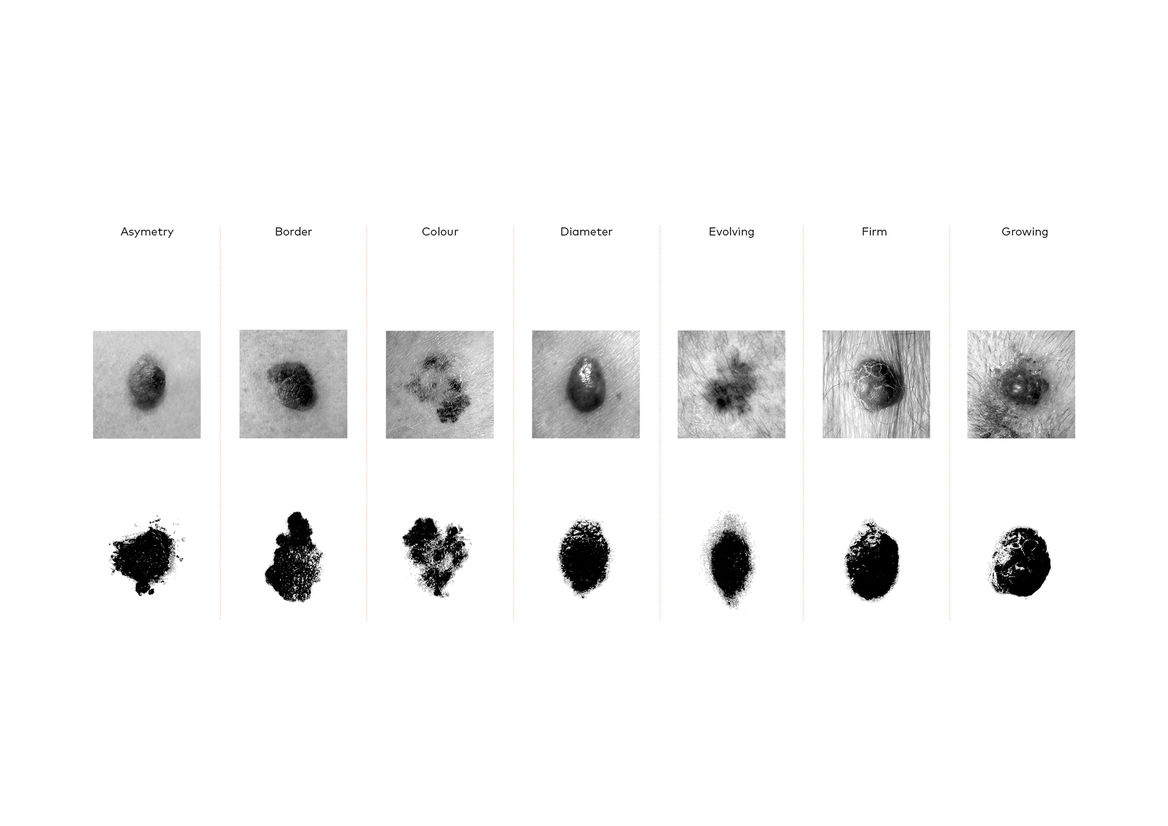

We created a usable font, made up of seven glyphs of a single character - the full stop. Each glyph was designed in partnership with New Zealand medical professionals to accurately represent one of the visual symptoms of Melanoma. When viewed at a small size, the glyphs all look like slightly misshapen full stops. But as point size increased, more and more detail is revealed in each character, until the true nature of each spot is impossible to ignore.